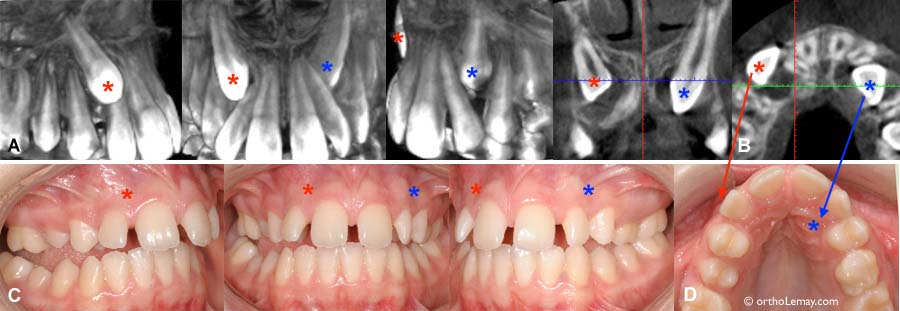

(A) Patient de 8.9 ans présentant des canines permanentes (* rouge) se présentant au dessus des racines des latérales (* bleus). L’extraction de dents temporaires dont les canines aiderait l’éruption des latérales et canines. (B) Un autre patient de 11.5 ans chez qui les canines temporaires ont été extraites. Les canines permanentes (* rouges) se redressent et descendent mais manque tout de même d’espace . Celle de droite se bute sur la latérale (* bleu) tandis que celle de gauche évite l’autre latérale. (C) Jeune femme de 20 ans pour qui il est trop tard pour intervenir avec une simple extraction de canine temporaire… qui aurait dû être extraite il y a au moins 10 ans!

8.2 ans

Ces 2 patients de 8 ans présentent une position des canines permanentes (* rouges) qui peut être favorablement influencée par des extractions sélectives (canines temporaires * bleus).

16.5 ans

Chez cette fille de 16 ans, les canines permanentes (* rouges) sont presque complètement vers le centre (et au palais). Cette situation était visible il y a plus de 7-8 ans et l’extraction des canines temporaires aurait certainement aidé la situation, sans “garantir” une éruption normale.